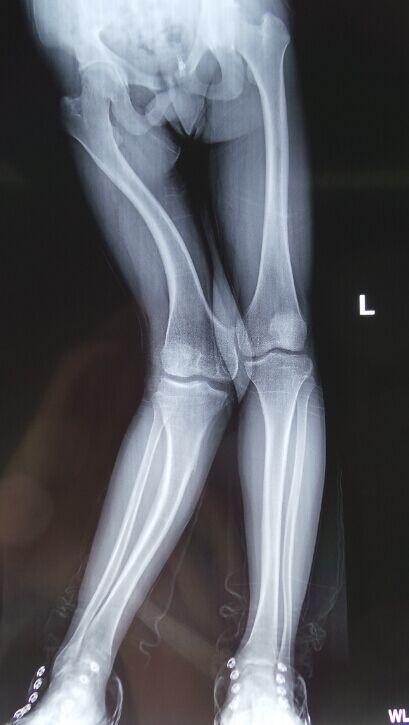

東望科技免費為右膝外翻畸形的患者打印模型,當患者看到自己的1:1腿骨模型的時候,才知道自己的病情是多么嚴重。

CT的平面二維數據不能夠準確的設計手術實施計劃,我們根據醫療影像數據打印出患者1:1腿骨模型, 醫生拿到模型后對患者的病灶“看得更清楚”,然后馬上進行手術設計,截骨角度尺寸等,都在模型上進行實際演練,最后設計出最終方案 。對3D打印并不了解的患者及其家屬看到模擬手術后,對手術的實施也更加放心了。

本來進行4-5個小時的手術,僅僅用了一個多小時就結束了。術后恢復相比于傳統手術,患者的恢復更快。